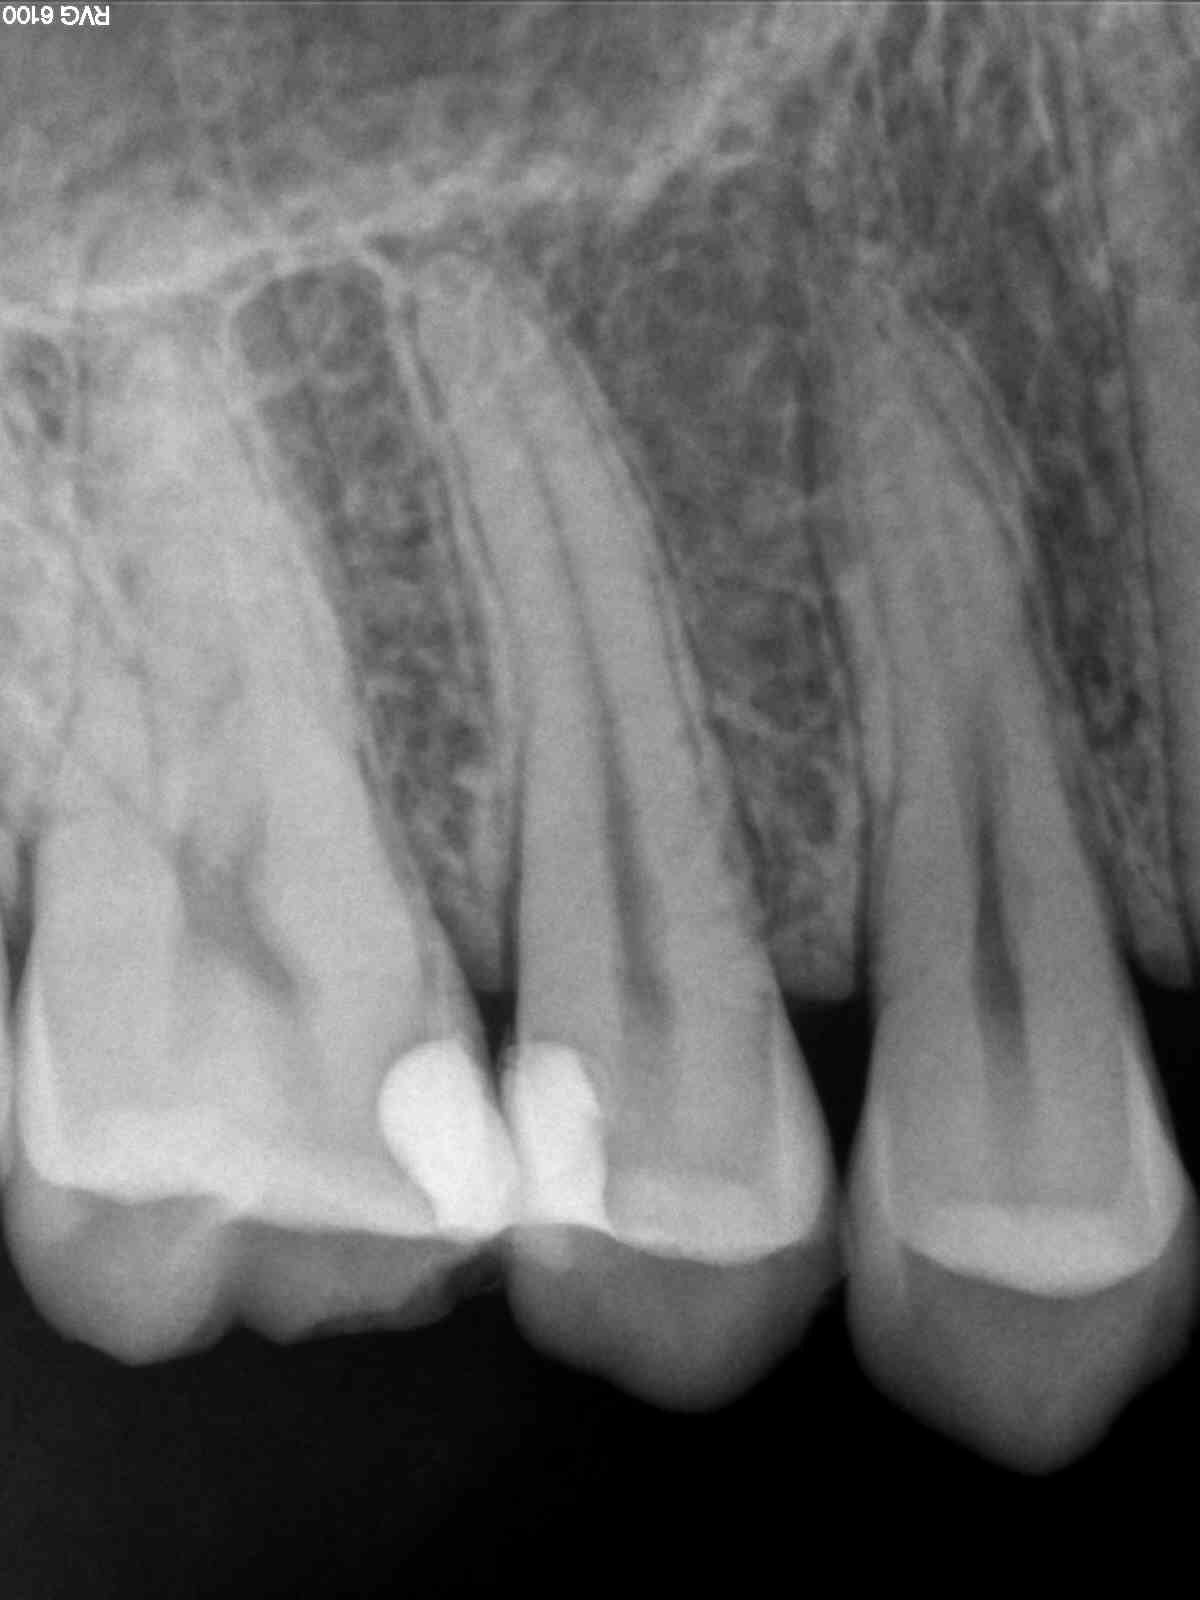

Bon, ça me fatigue ce capteur, je ne sais plus interpréter mes Rx ...

Sérieusement vous voyez quelque chose sur le deuxième cliché ?

Le premier pris il y a 2 mois, lors de l'endo avec le trophy, et le deuxième cliché avec le kodak, je n'arrive pas à dire si c'est en voie de guérison :((

Même avec le filtre de netteté, en bidouillant les contrastes, j'y vois quedal :(